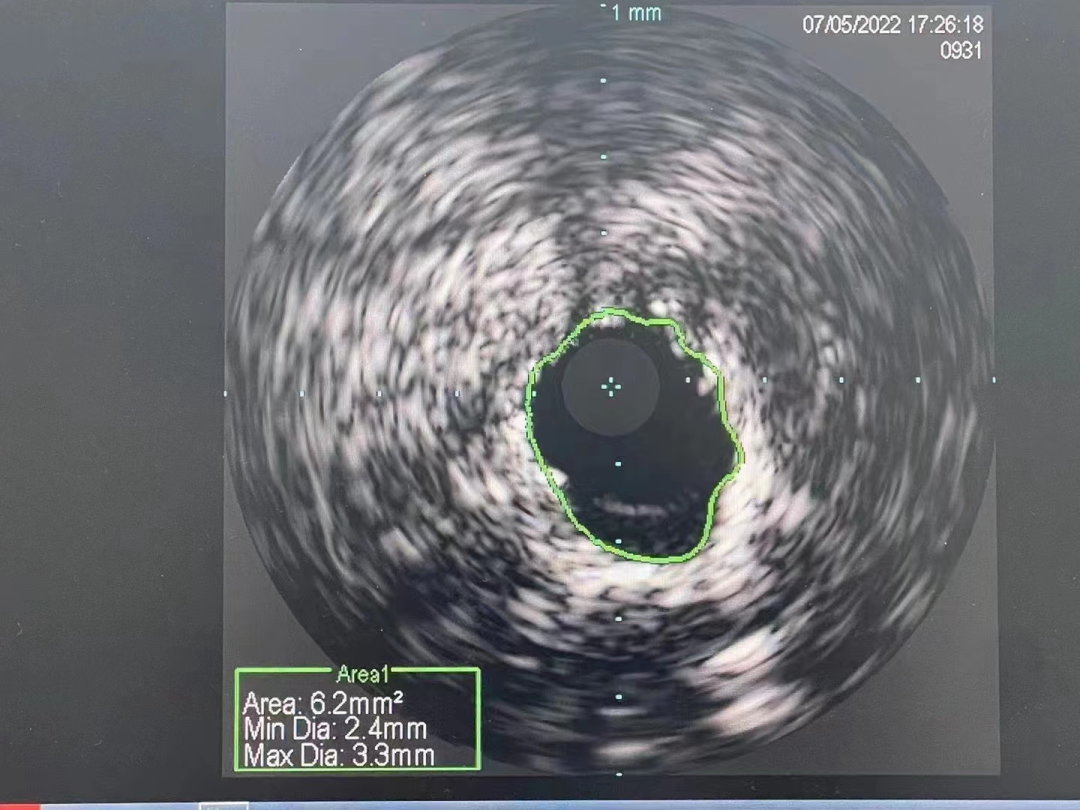

冠脉内介入治疗